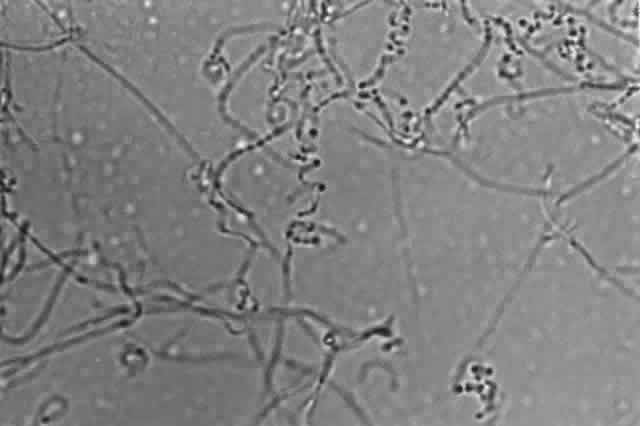

ACREMONIUM SPECIES (CEPHALOSPORIUM SPECIES).

Growth matures within 2 to 6 days. Colonies are white, pink, or gray. Reverse is colorless, pale yellow, or pinkish. Texture is moist, spreading, becoming woolly with age. Microscopic findings include slender, delicate septated hyphae. Conidiophores are simple and erect with one-celled, occasionally two-celled, conidia arranged in clusters at the tips.